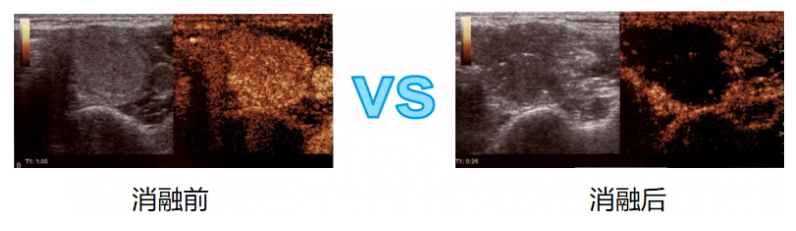

3、最新的造影技术即刻评估消融范围,确保病灶完全消融。

【造影技术】

使用造影剂后散射回声增强,明显提高超声诊断的分辨力,敏感性和特异性的技术。在甲状腺乳腺结节消融前、中、后的评估都起到了重要作用。消融前治疗规划:

※ 优于常规超声。

※ 准确反映甲状腺结节微循环灌注。

※ 设计最佳进针路线。

※ 分辨甲状腺和周围组织的结构关系。